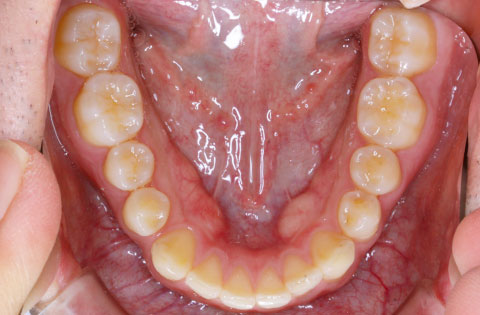

矯正前 下顎

矯正後 下顎